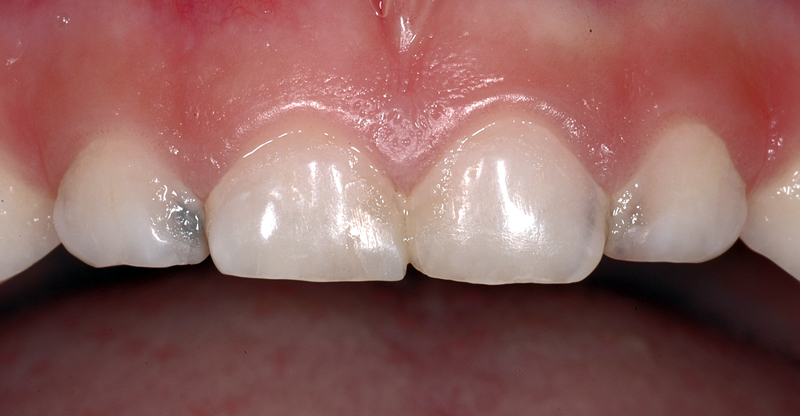

In diesem Beispiel sind dunkle Flecken «vorne» (mesial) an den seitlichen Milchschneidezähnen (Zähne 52 und 62) zu sehen; rechts grau-schwarz, links mehr braun.

Diese Zähne haben Karies in den Zahnzwischenräumen.

Zudem sind Füllungen in der Mitte bei den zentralen Schneidezähnen zu sehen.

- dunkle Flecken an den seitlichen Milchschneidezähnen